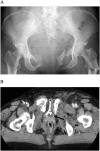

Pelvic circumferential compression devices (PCCDs) have gained wide acceptance in the management of patients with pelvic fracture. These devices are considered safe due to their noninvasive nature and significant hazards associated with the use of PCCDs have not been reported previously. However, we present herein the cases of three patients who received PCCD application and eventually developed major complications presumably caused by PCCDs. As a result, one patient developed surgical site infection following internal fixation and required several debridements. Another patient ended up with a walking disability. The remaining patient eventually died from exsanguination following application of the PCCD. Clinicians should be aware of the potential for deleterious effects, including bladder rupture, muscle necrosis, and vessel injuries. In particular, application for acetabular fractures and prolonged application of PCCDs should be avoided.